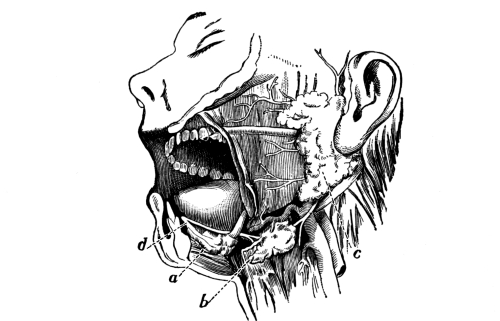

The Cranial Bones, 48—Frontal Bone, 49—Parietal Bones, 49—Occipital Bone, 50—Occipito-frontalis Muscle, 51—Temporal Bones, 51—Sphenoid or Wedge Bone, 52—Ethmoid Bone, 53—Turbinated Bones, 53—Ossification of Sutures, 53—Bones of the Face, 53—Superior Maxillary Bones, 54—Antrum of Highmore, 54—Malar or Cheek Bones, 54—Lachrymal Bones, 54—Palate Bones, 54—Nasal Bones, 55—Vomer, 55—Inferior Turbinated Bones, 55—Inferior Maxillary Bone or Lower Jaw, 55—Sublingual Gland, 56—Submaxillary Gland, 56. |

| The Organs of Special Sense | 57 |

The Nose, 57—The Sense of Smell, 58—The Mouth, 59—The Hyoid Bone, 60—The Teeth, 60—The Sense of Taste, 61—Salivary Glands, 61—The Tonsils, 62—The Ear, 63—Eustachian Tubes, 63—Sensation of Hearing, 65—The Eye, 66—Lachrymal Gland, 68—Coats of the Eye, 68—Light Rays and Sight, 70—Accommodation, 72—Color Perception, 73. |